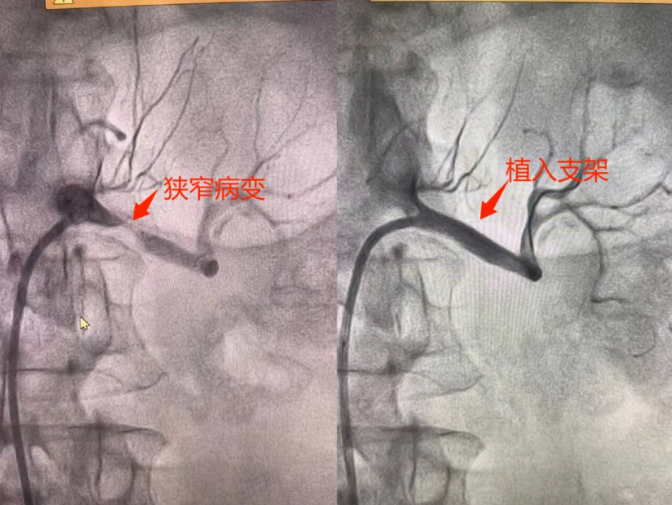

微創(chuàng)介入,立竿見影為有效控制血壓,避免腎功能進(jìn)一步受損,心血管內(nèi)科團(tuán)隊(duì)為患者制定了詳細(xì)的治療方案,行冠狀動(dòng)脈造影同時(shí)行腎動(dòng)脈造影檢查進(jìn)一步明確患者冠脈及腎動(dòng)脈血管情況,根據(jù)冠脈造影結(jié)果給予冠狀動(dòng)脈支架植入術(shù),根據(jù)腎動(dòng)脈造影結(jié)果給予患者行左腎動(dòng)脈支架植入術(shù)。在介入導(dǎo)管室的配合下,手術(shù)團(tuán)隊(duì)通過(guò)微創(chuàng)介入技術(shù),成功為患者同時(shí)植入了腎動(dòng)脈支架及冠脈支架,恢復(fù)了冠狀動(dòng)脈及腎動(dòng)脈的正常血流。術(shù)后,患者血壓迅速下降,胸痛癥狀明顯緩解,術(shù)后血壓穩(wěn)定在正常范圍,患者恢復(fù)良好。